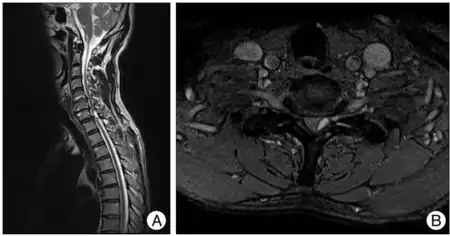

| a,b)Brown-séquard syndrome caused by a cervical synovial cyst. | |

Magnetic resonance imaging (MRI) is the imaging of choice in spinal cord lesions.